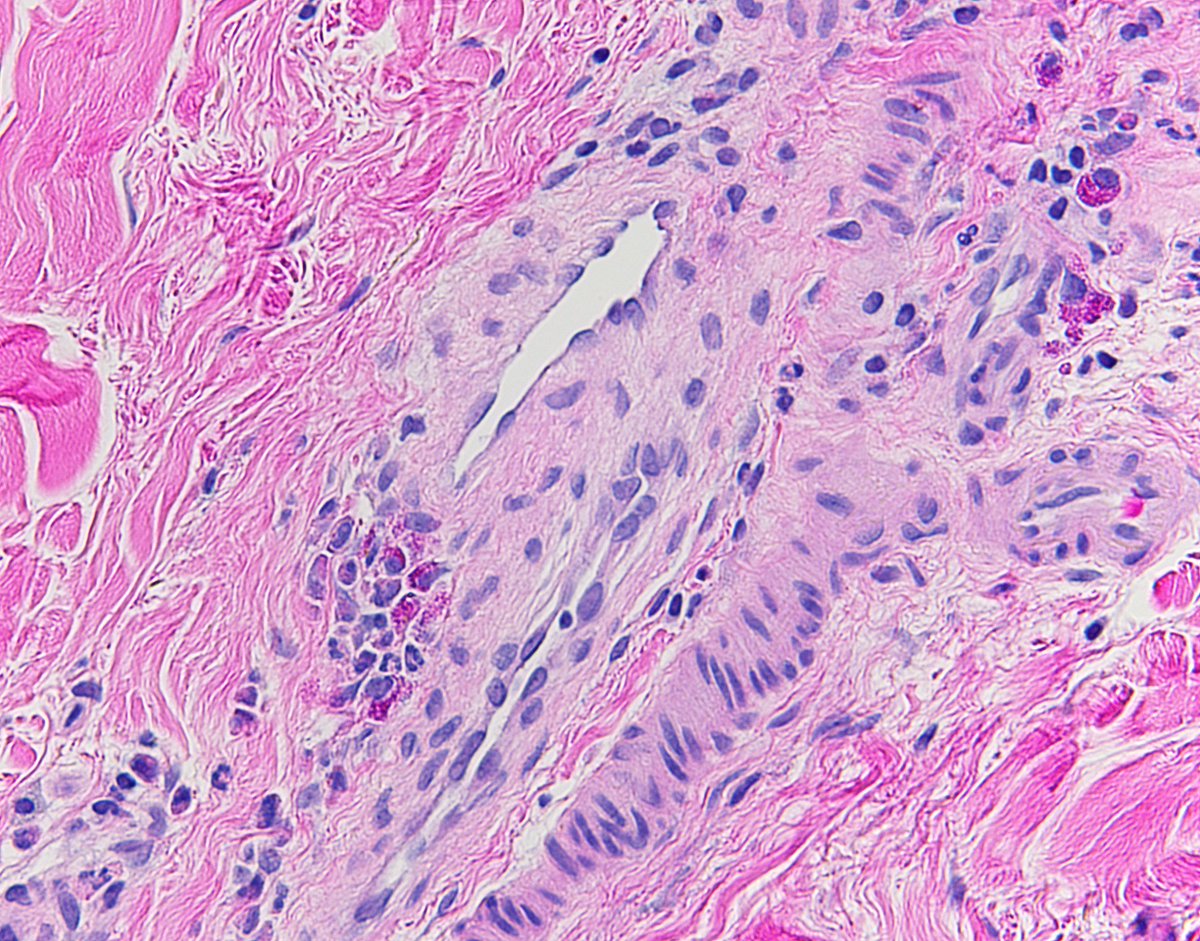

Breast skin biopsy - superficial green circle with urticarial inflammatory reaction suggests all okay, but deeper red circle shows metastatic breast CA. Biopsy size = biopsy accuracy #dermatology #breastcancer